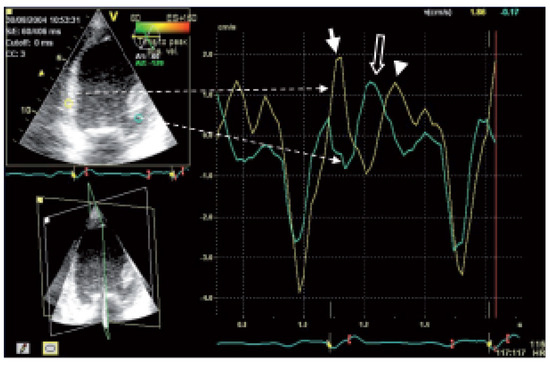

Gewebedoppler-Echokardiographie